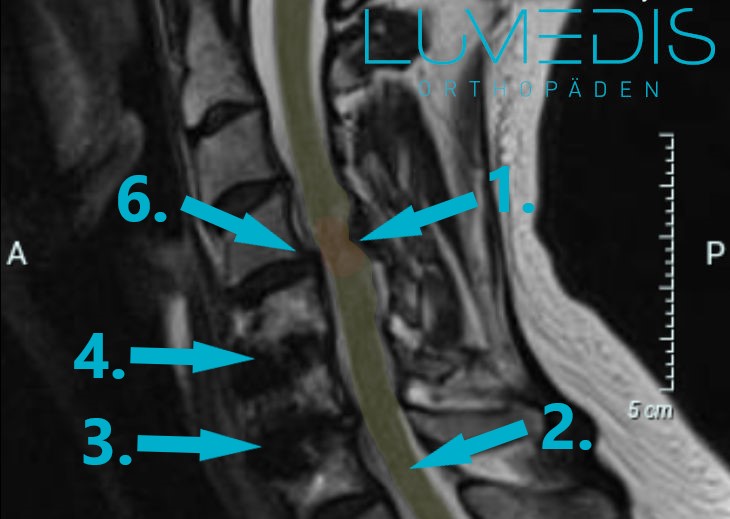

MRT der LWS (T2, seitlich)

Abbildung eines Bandscheibenvorfalls

MRT der LWS (seitlich, T2) mit einem Bandscheibenvorfall L5/S1: